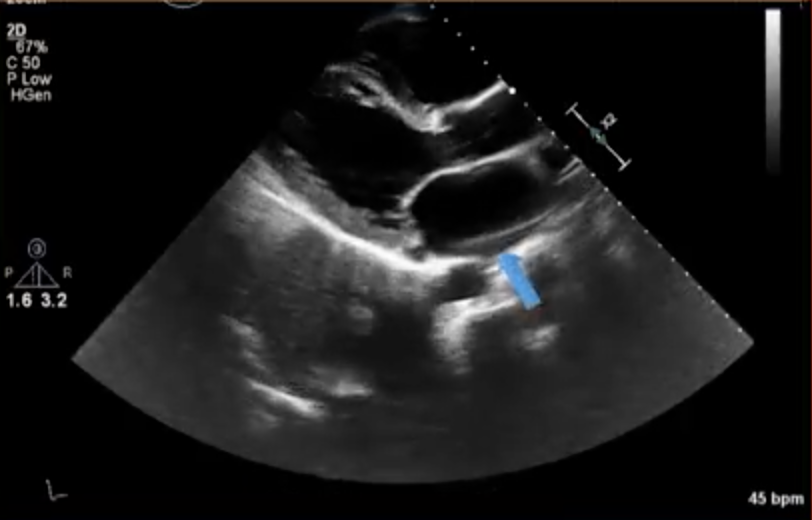

What kind of artifact is illustrated here?

Acoustic shadowing – cause by failure of ultrasound beam to pass through an object resulting in a dark area distal to the reflective/attenuating surface